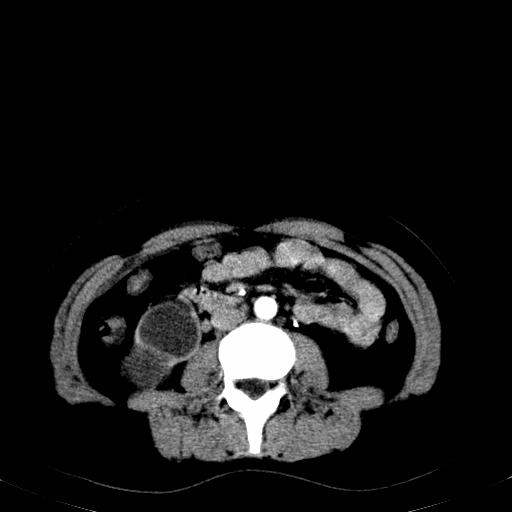

患者体检发现右肾体积增大,怀疑右肾积水

右肾重度积水,以肾盏积水明显,有分隔,上段输尿管轻度扩张,管壁增厚,考虑肾结核可能,请结合尿检查,胸部拍片排除肺结核。

右肾重度积水,建议ct向下扫描或逆行造影,左肾及左输尿管结石 .

患者尿常规正常,b超未发现明显结石,自身也无明显感觉异常。

请问多囊肾与肾积水怎么鉴别